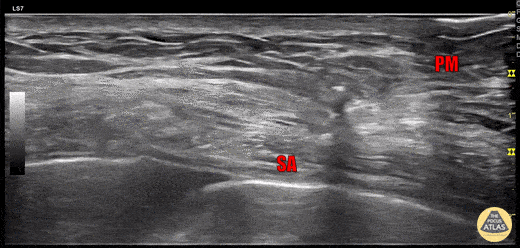

60s F presented to the ED three days after a fall at home, complaining of right chest pain, and was found to have multiple rib fractures on CT with a small amount of hemothorax and blood in the horizontal fissure. A serratus anterior plane block was performed using an in-plane approach to inject anesthetic in the fascial plane between the pectoralis minor (PM) and serratus anterior (SA) muscles. Fluid can be seen in the pleural space beneath serratus anterior. 30 minutes after the nerve block, the patient was feeling much improved, her performance on incentive spirometry improved markedly, and she requested discharge. Dr. Michael Heffler, PGY3 Denver Health Residency in Emergency Medicine